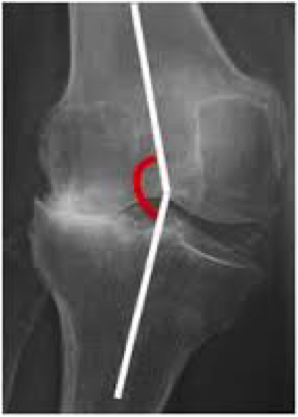

La maniobra de varo-valgo a 0 y 30º

Se fuerza la rodilla hacia fuera o hacia adentro, haciendo rebotes suaves, no buscando el límite ni una deformidad enorme de la rodilla lesionada y sintiendo la laxitud de la rodilla con estas maniobras.

En flexión, el LCA (ligamento cruzado anterior) no estabiliza a la rodilla en dirección medial y lateral pero si hacemos una extensión completa el LCA se tensa y estabiliza totalmente la rodilla.

Por lo tanto un bostezo a 30º indica distensión o esguince del ligamento colateral correspondiente, pero no del LCA. Si hay bostezo franco en extensión indica rotura del LCA y del ligamento colateral correspondiente.

Si hay una rotura aislada del Ligamento colateral medial pero el Ligamento Cruzado Anterior está íntegro, habrá un mínimo bostezo en extensión y un bostezo franco a 30º de flexión.